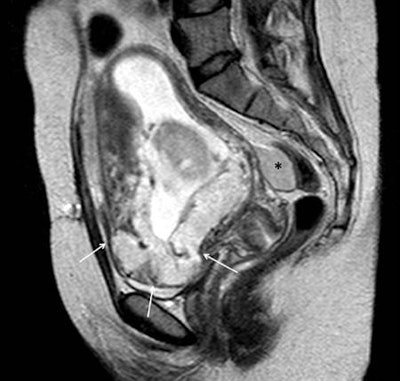

Sagittal single-shot T2-weighted image through the pelvis in a 16-week gestational age pregnant woman with acute onset of hypotension and vaginal bleeding. A placenta previa was identified with an abnormal contour of the inferior part of the uterus and loss of visualization of the normal uterine wall (arrows). Additionally, a bloody collection was identified in the rectouterine recess (*). Uterine rupture was confirmed intraoperatively.Previous uterine surgery predisposes to abnormal adherence or penetration of the chorionic villi to or into the uterine wall, the extent of which further subdivides the "abnormal" placenta to placenta accreta (superficial invasion of the basalis layer), placenta increta (deeper invasion of the myometrium), and placenta percreta (even deeper invasion of the serosa or adjacent pelvic organs), which may lead to thanatophoric hemorrhage at the time of the placental delivery, often necessitating emergent hysterectomy, the researchers stated.